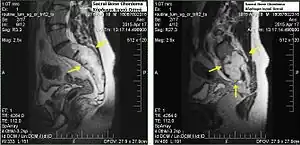

.jpg)

Chordomas can arise from bone in the skull base and anywhere along the spine. The two most common locations are cranially at the clivus and in the sacrum at the bottom of the spine.[2]

Sacral chordoma is presented with chronic low back pain.[3]